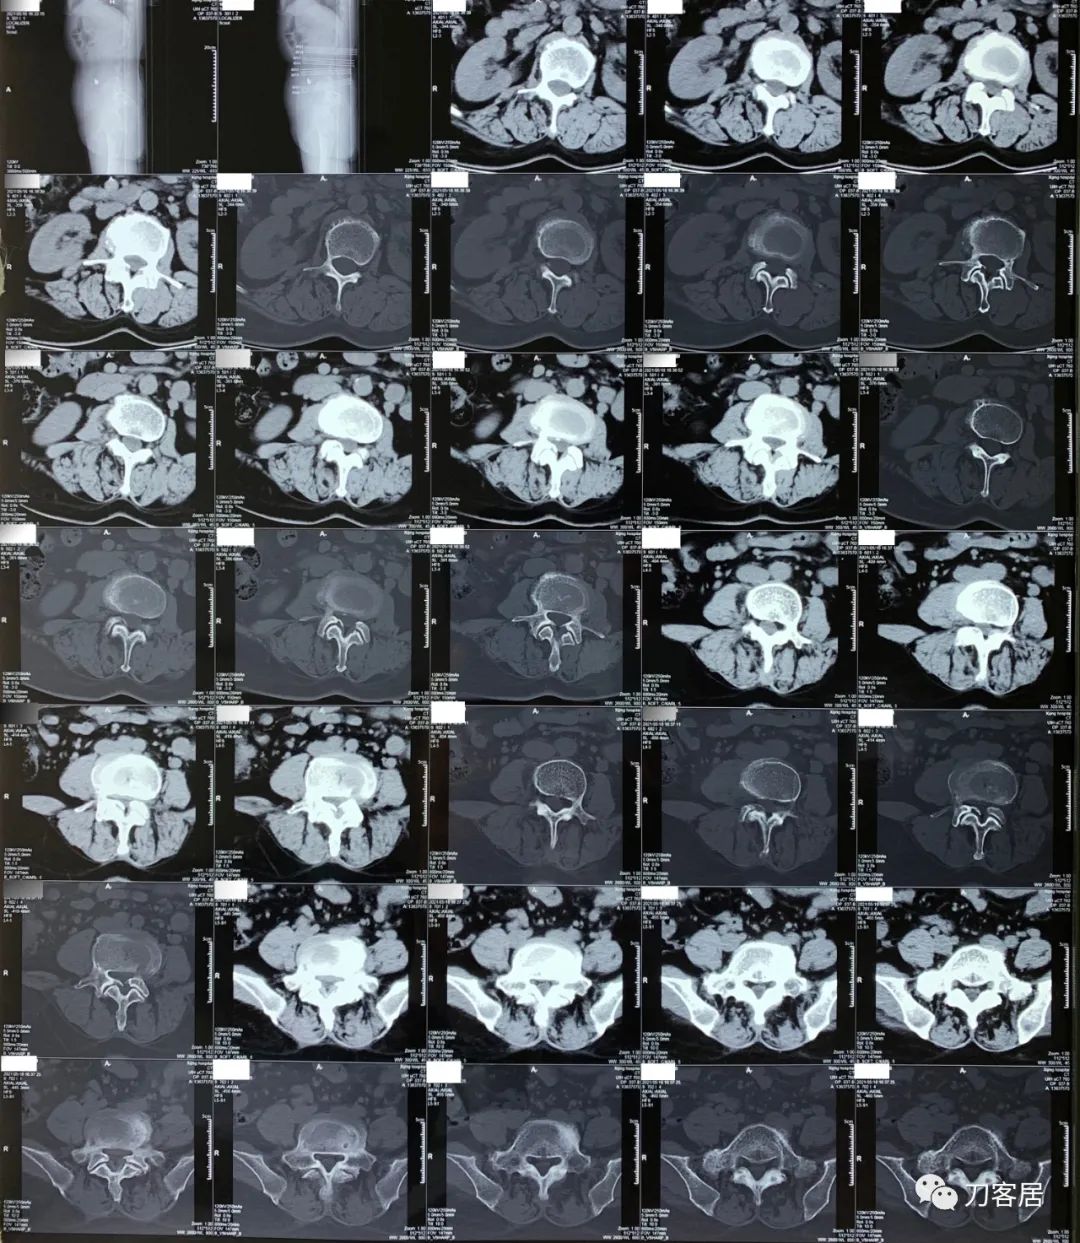

2021年5月17日,西京医院骨科门诊找我就诊,自带影像学检查资料提示腰椎侧弯,腰3-4,腰4-5椎间盘突出,黄韧带肥厚,椎管狭窄。

建议其查双光子骨密度,骨盆正位片以及腰椎间盘平扫。腰椎正侧位X线片以及动力位片,站立位脊柱全长正侧位X线片,以了解其是否有骨质疏松,并了解脊柱侧弯情况,腰椎局部X线表现情况和腰椎间盘突出和椎管狭窄情况。

从这个患者的影像资料分析,颈椎间盘突出问题不大,没有明确的上位神经元损伤表现,所以,不考虑颈椎和胸椎问题。腰椎侧弯畸形,但不严重。因为存在腰椎侧弯,使得腰椎MRI在扫描切面的时候,显示的椎间盘突出或椎管狭窄会有一定的误差,所以,又加做了经椎间盘的CT平扫,影像表现并不严重,综上,腰椎间盘突出,腰椎管狭窄,腰椎侧弯,不考虑手术治疗。同时,患者的主要痛苦是心理疾病,而不是器质性疾病,所以,以心身疾病治疗为主。虽然患者骨密度检查结果提示正常,但X线片显示骨质疏松,且其症状也与骨质疏松的症状有符合之处,比如静息痛,不能入睡,动作及姿势变换时痛加重等,所以,给予实验性抗骨质疏松治疗,以观疗效。